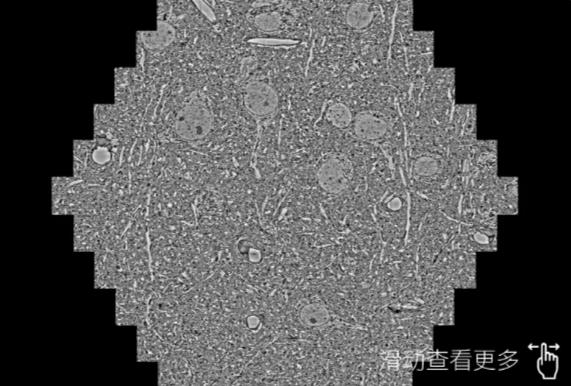

鼠脑切片。左图使用文山蔡司文山扫描电镜MultiSEM706对165μmx143pm面积区域成像,耗时仅需1.5秒。右图为鼠脑切片中30μm区域放大效果。样品由芝加哥大学B.Kasthuri提供。

使用蔡司高速文山扫描电镜MultiSEM对1mm²人脑皮层组织进行高分辨成像,并对其中的各种细胞结构进行三维重构分析。左图展示了2x3mm²组织平面中锥体神经元的三维重构效果。右图显示了局部体积神经元三维重构。图像由哈佛大学chtman实验室提供,渲染图由D. Berger 制作。